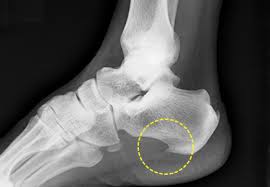

족저 근막염은 발바닥의 족저 근막에 반복적인 스트레스가 가해져 염증이 생기는 질환입니다. 이로 인해 발바닥, 특히 발뒤꿈치 부분에 통증이 발생하는데, 주로 아침에 일어났을 때 가장 심한 통증을 느끼게 됩니다. 족저 근막염은 비만, 운동 부족, 잘못된 신발 착용 등 다양한 원인으로 발생할 수 있는데, 이러한 원인을 파악하고 족저 근막염 치료법을 적용하는 것이 중요합니다. 통증이 심해지면 일상생활에 큰 지장을 초래할 수 있으므로 조기에 치료하는 것이 좋습니다.